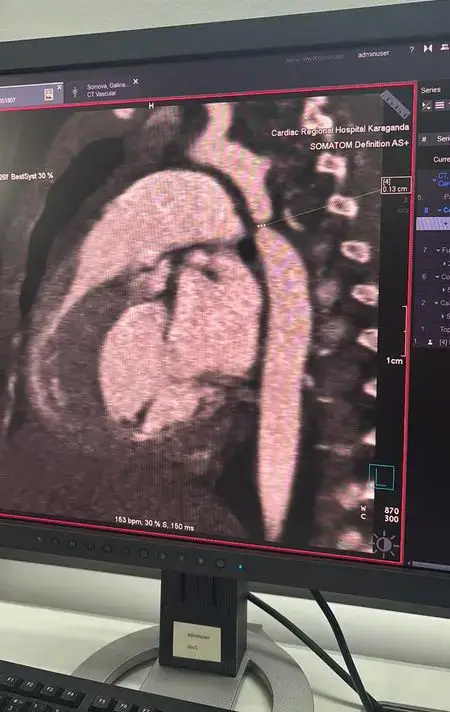

В Караганде в многопрофильной больнице №2, известной как Кардиоцентр, была успешно проведена сложная операция на сердце трёхмесячной девочке. Эта операция стала значимым событием для региона, так как это первая подобная процедура, выполненная в стенах данной больницы. Малышка была госпитализирована с диагнозом пневмония, однако обследование выявило более серьёзную проблему — критическую коарктацию аорты, которая требует немедленного хирургического вмешательства.

После установления диагноза девочку экстренно перевели в Кардиоцентр, где был проведён консилиум с участием специалистов из Астаны. В операционную были приглашены ведущие кардиохирурги, включая Галымжана Утегенова и анестезиолога Хафиза Ахмерова из University Medical Center. Операция, продолжавшаяся почти пять часов, заключалась в резекции коарктации аорты и наложении анастомоза "конец в конец", что позволило восстановить нормальный кровоток.